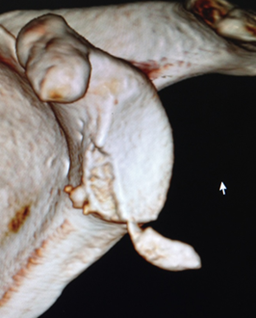

肩关节Bony-Bankart损伤

肩关节镜下缝合修复Bony-Bankart术后